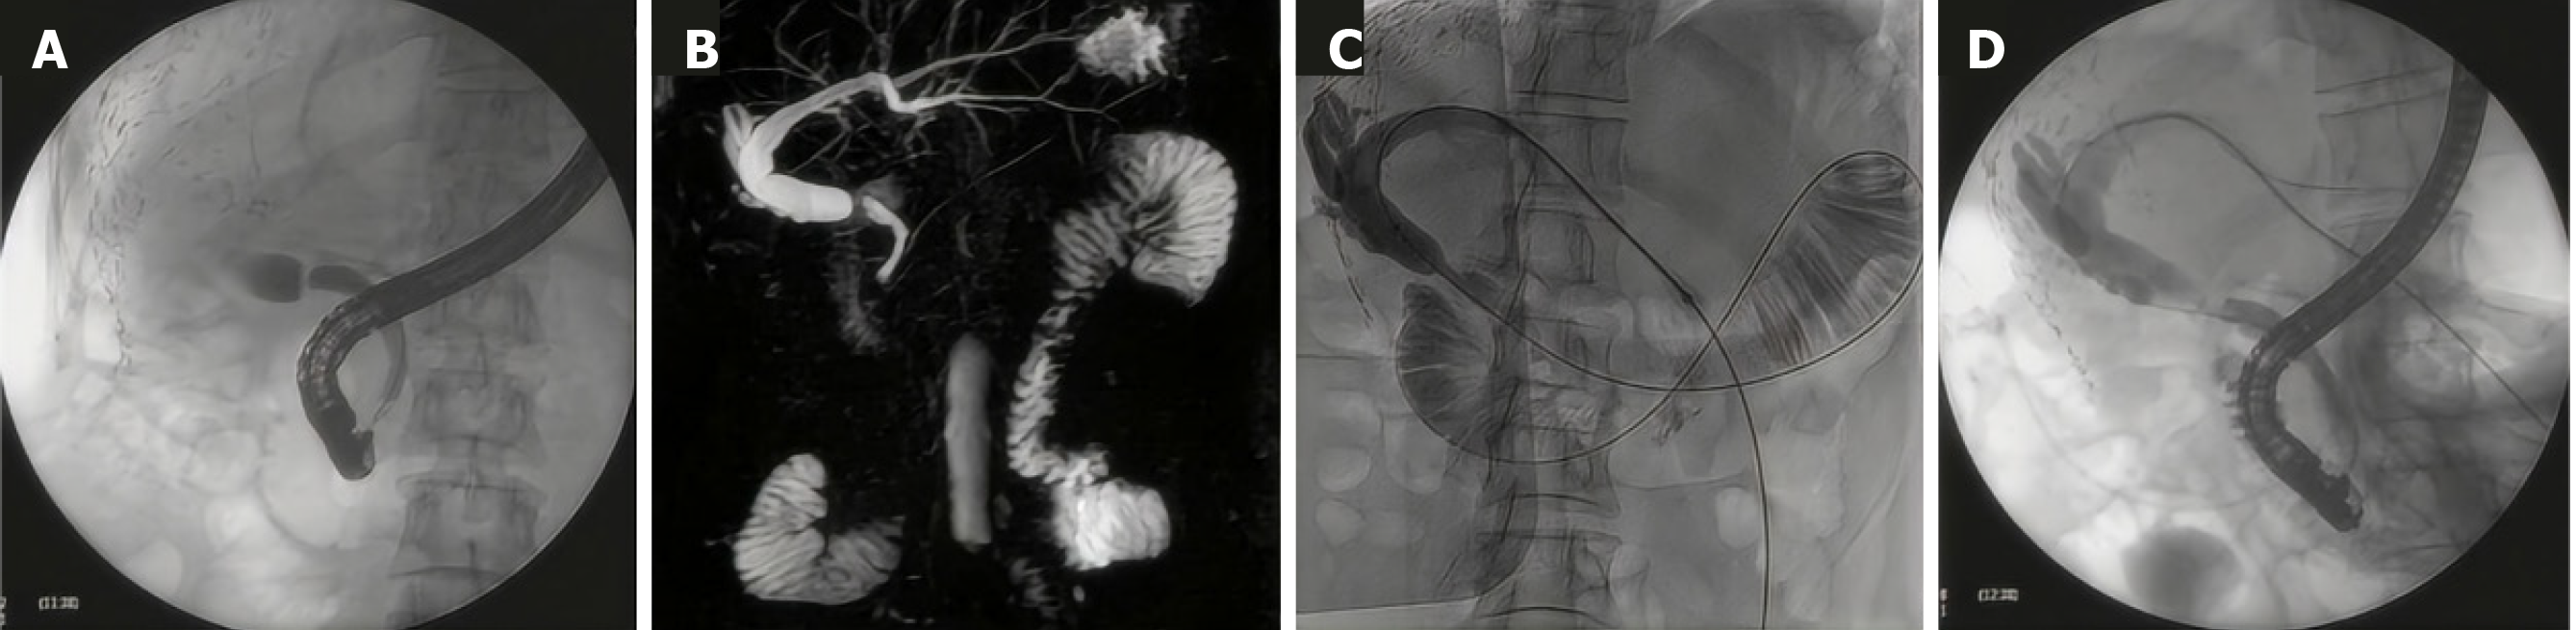

胆管吻合口狭窄作为肝移植术后最为常见的并发症之一, 是导致肝功能衰竭及受体死亡的重要因素. 据研究统计, 其发病率介于4%-9%之间[1]. 目前, 针对胆管吻合口狭窄的治疗方法主要包括治疗性内镜逆行胰胆管造影术(endoscopic retrograde cholangiopancreatography, ERCP)、经皮经肝穿刺胆道引流术(percutaneous transhepatic cholangial drainage, PTCD)以及外科手术[2], 其中ERCP被广泛视为首选治疗方案[3-5]. 然而, 对于部分中高位胆管狭窄或胆管狭窄程度较为严重的患者, ERCP插管可能无法顺利通过狭窄部位, 并增加了产生急性胰腺炎的风险. 此时, 可联合应用PTCD技术, 通过顺行方式插入导丝穿越狭窄区域, 采用会师技术[6], 从而成功实现ERCP插管, 解决胆管狭窄问题(图1). 但该技术在临床上应用并不广泛. 本文旨在报道3例ERCP插管未获成功的病例, 详细阐述了采用经皮经肝穿刺置入导丝联合ERCP(即会师技术)治疗肝移植术后胆管狭窄患者的诊疗过程.

患者于2024-10-12接受ERCP治疗. 术中导丝无法通过狭窄部. 由于ERCP置入支架无法直接完成, 患者于2024-10-17接受PTCD治疗, 于左肝胆管内置入引流管, 引流通畅. 2024-10-18, 患者复查肝功能, 结果显示肝功能指标有所改善: ALT 38.3 U/L, AST 31.2 U/L, ALP 266.2 U/L, GGT 163.5 U/L, 总胆红素16.33 mmol/L, 直接胆红素6.09 mmol/L. 同日上午, 患者行胆道狭窄球囊扩张及引流管置入术. 术中, 经原引流管造影, 提示肝内胆管扩张、胆总管吻合口段狭窄. 随后, 经导丝于狭窄处置入球囊进行扩张. 扩张完毕后, 将导丝留置于肠腔, 以备ERCP置入胆道支架. 支架植入完毕后, 再在数字减影-血管造影(digital subtraction angiography, DSA)引导下, 于胆管内置入胆道外引流管. 手术顺利, 引流通畅. 同日下午, 患者再次接受ERCP术. 术中透视见经皮穿刺导丝已在肠腔成圈. 沿导丝置入探条通过吻合口, 放置塑料支架进行引流并固定支架.

2024-08-28尝试行ERCP, 但导丝在直视下反复探插均无法通过吻合口. 2024-09-03行肝脏MRCP检查, 结果显示肝内胆管扩张, 胆管吻合口处胆管显影不清, 管腔狭窄. 鉴于胆道吻合口狭窄导致ERCP置入支架无法直接完成, 遂于2024-09-06行PTCD, 术中胆道造影显示肝内外胆管扩张, 胆总管中上段梗阻. 随后利用导丝导管技术越过胆总管中段狭窄处, 将鞘管留置于狭窄远端. 同日下午, 患者再次行ERCP, 术中自穿刺鞘管置入导丝并自开口插出, 探条对接后, 沿导丝置入深条通过吻合口, 成功在右前叶放置改制支架及塑料支架.

2024-07-10, 患者接受ERCP治疗, 但导丝反复尝试超选后, 位置无法确定, 操作遂结束. 2024-07-11, 患者行经皮移植肝胆管穿刺置管术, 引流通畅. 2024-07-17, 经原PTCD管行胆道造影, 提示胆管吻合口处可见一线样狭窄. 随后, 在DSA引导下, 利用导丝导管技术成功越过胆管狭窄处, 留置鞘管和导管导丝, 并妥善固定. 同日, 患者再次接受ERCP术, 于内镜下完成胆管导丝对接、胆管扩张及支架置入.